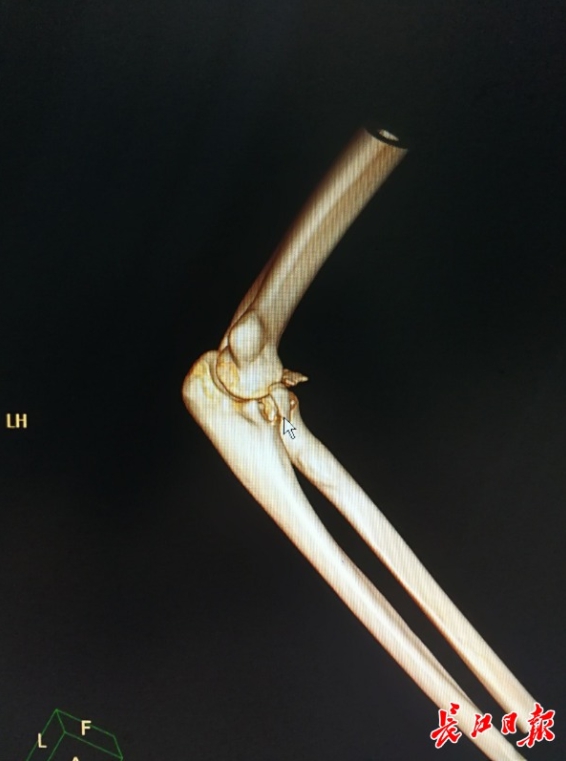

▼醫師檢查完就確認的右臂骨折,還說他的右手肘骨折脫位,韌帶也有問題,必須要接受手術治療才可以完全康復。